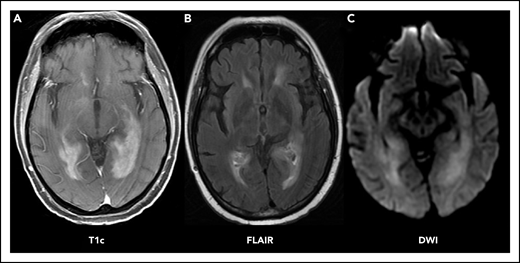

Patients with neurologic signs or symptoms as described above should immediately undergo brain imaging. The preferred imaging modality is magnetic resonance imaging (MRI) with and without contrast. MRI provides the best resolution for visualization and may be helpful with diagnosis of PCNSL, because it is often associated with characteristic radiographic features (Figure 1A). Lesions may be multifocal or unifocal. They are often periventricular (60%), affecting deep brain structures like the corpus callosum, the deep white matter, or the basal ganglia. On T2 sequencing, they tend to be iso- to hyperintense (Figure 1B) and are typically homogeneously enhancing with associated diffusion restriction (Figure 1C). In contrast to glioma or solid tumor metastases, PCNSL lesions tend to present with a mild amount of edema relative to their size.6 In patients who are unable to tolerate MRI scans, a computed tomography (CT) scan with and without contrast may be performed. The role of FDG–positron emission tomography (PET) brain imaging has not been established.8 PCNSL can present with isolated leptomeningeal or ocular involvement, although this is rare. Still, a normal-appearing MRI should not preclude lumbar puncture and ocular examinations when suspicion remains.

PCNSL imaging pattern on MRI. Characteristic PCNSL imaging features on MRI. (A) T1 sequence with gadolinium contrast (T1c) demonstrates homogenously enhancing lesions affecting the deep white matter. (B) Fluid-attenuated inversion recovery (FLAIR) sequence demonstrates moderate edema surrounding the lesion. (C) Diffusion-weighted imaging sequence (DWI) demonstrates restricted diffusion within the lesions.